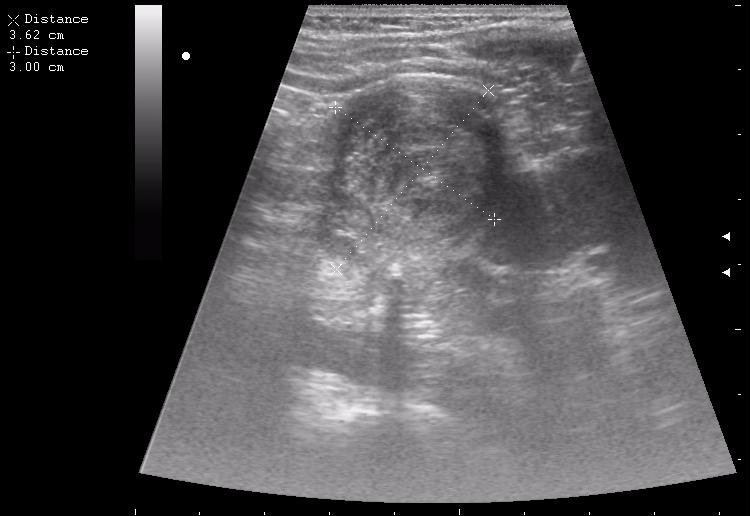

Гематома почки

нижний полюс